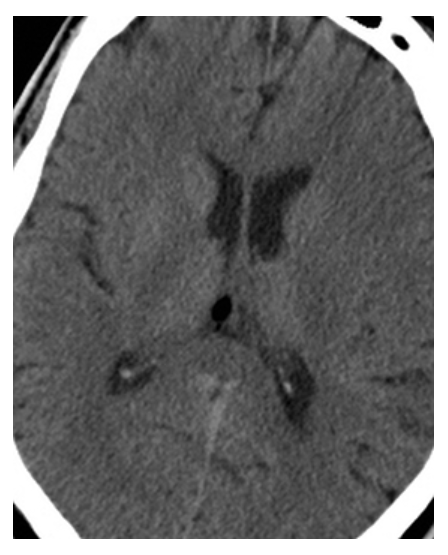

What is A

Glioblastoma Multiforme. Pre-axial CT images show a large peripherally enhancing centrally necrotic mass in the right frontal lobe which is extending across the white matter tracts of the anterior corpus callosum. Note the surrounding edema and mass effect resulting in midline shift.

What is B

Glioblastoma Multiforme. postcontrast axial CT images show a large peripherally enhancing centrally necrotic mass in the right frontal lobe which is extending across the white matter tracts of the anterior corpus callosum. Note the surrounding edema and mass effect resulting in midline shift.